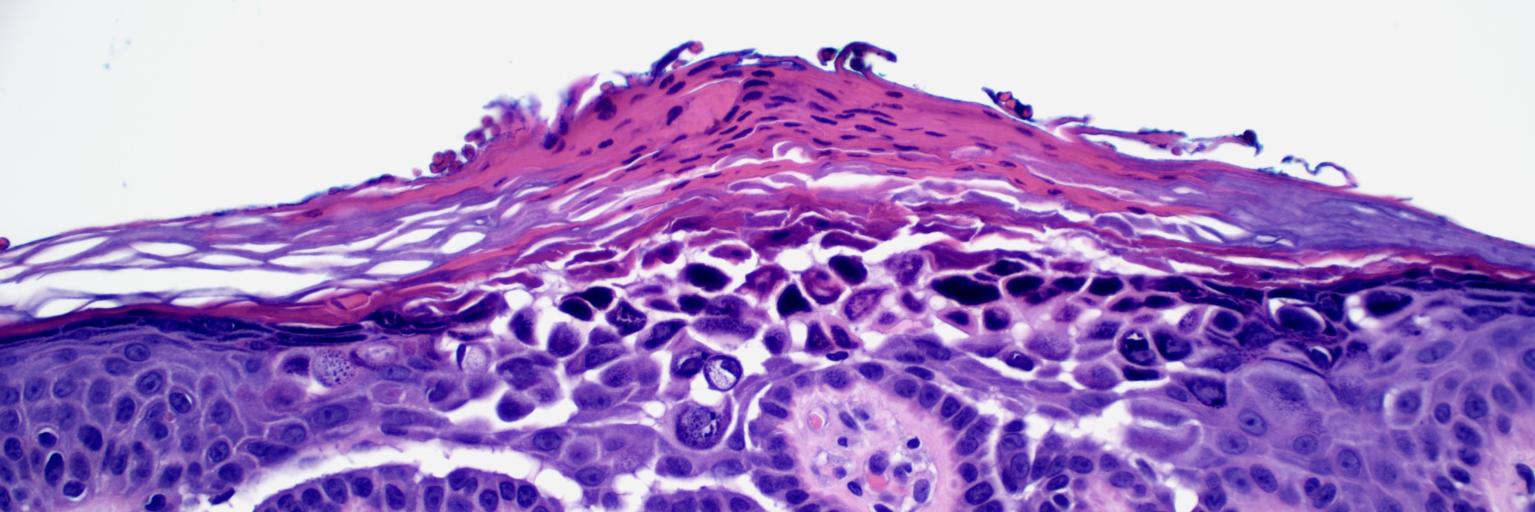

A recent case seen by @MattPowellMD, elderly patient with months of itching and now tense bullae. What antibodies could this be? #PathTwitter #path2path #PathMatch21

English